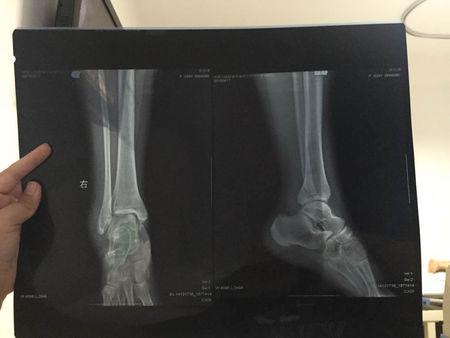

脚骨折片子,骨折片子

到医院拍了片子,医生说骨折了,片子显示右脚踝骨折两处.

脚踝骨折

胫腓骨骨折